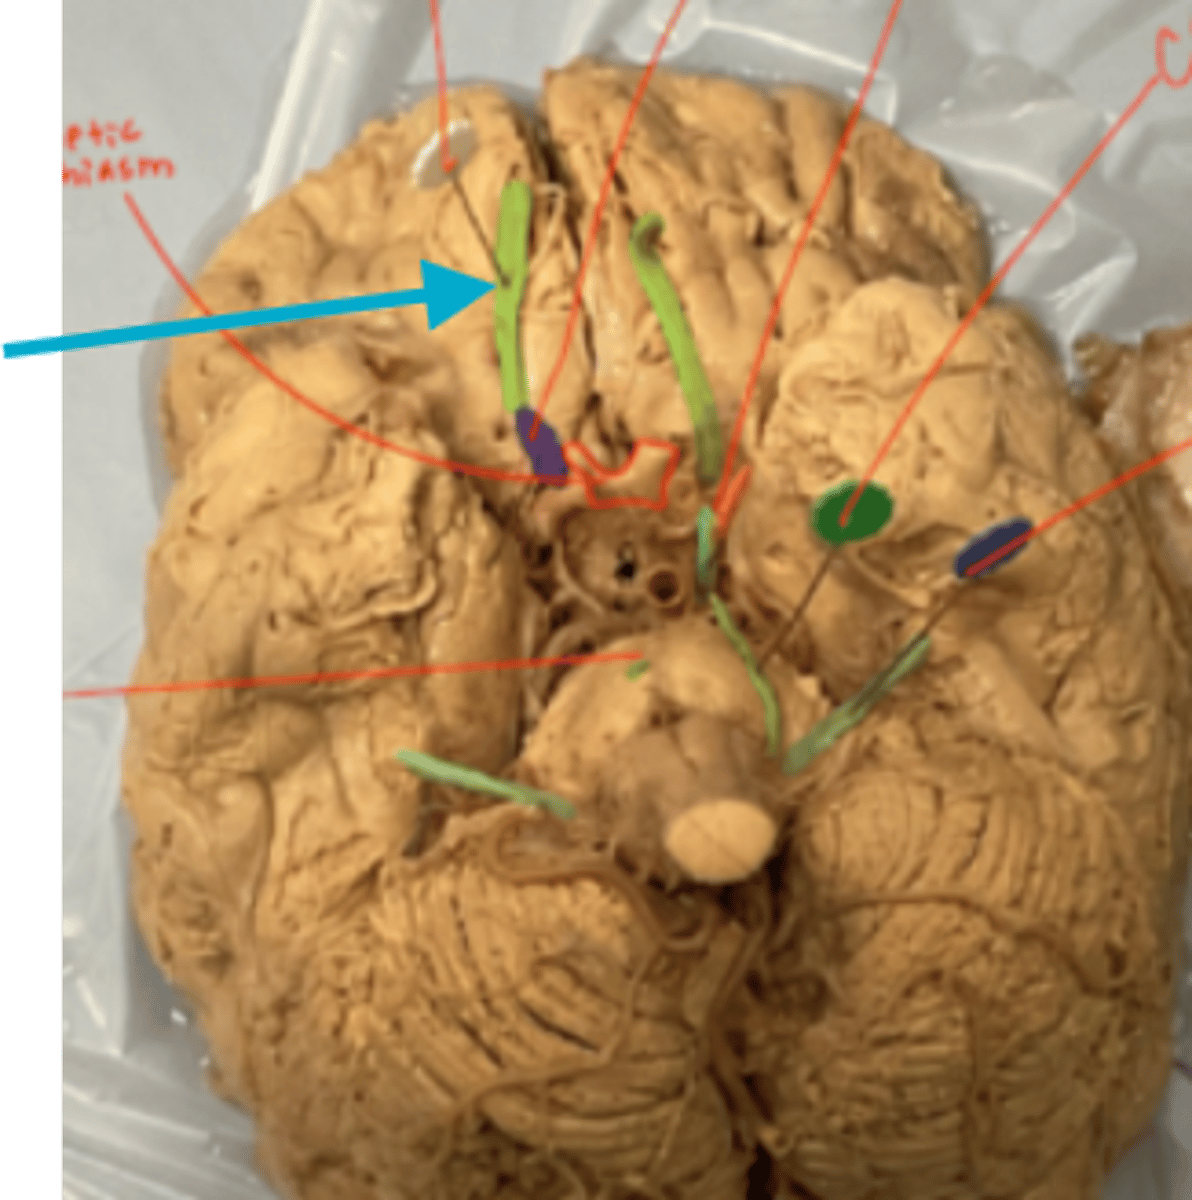

What is the blue arrow pointing at?

what is the blue arrow pointing to?

blue arrow is pointing to which structure?

The area the blue arrow is pointing to?

structure blue arrows are pointing to?

What area is the blue arrow pointing to?